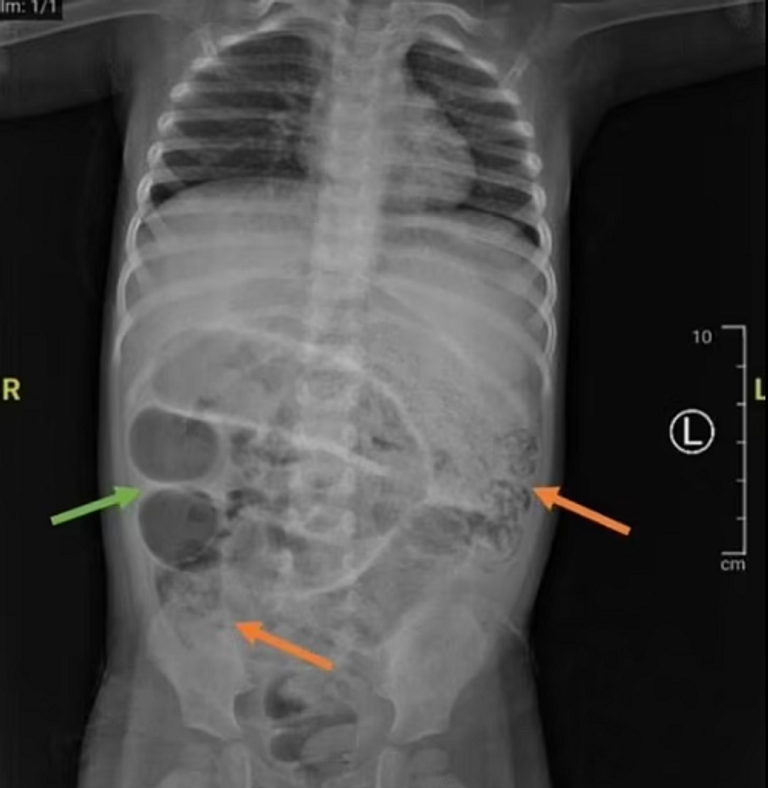

سرعان ما كشف فحص بالأشعة السينية عن كتل رمادية كثيفة في بطنه، مما دفع الأطباء إلى الاشتباه في انسداد معوي خطير، وكشفت جراحة طارئة لاحقة عن السبب المُروع، وهو عشرات من ديدان الإسكارس اللومينية، وهي ديدان أسطوانية كبيرة، يصل طول بعضها إلى 35 سنتيمرا، قد تشابكت في ثلاثة أجزاء مُنفصلة من أمعائه الدقيقة.